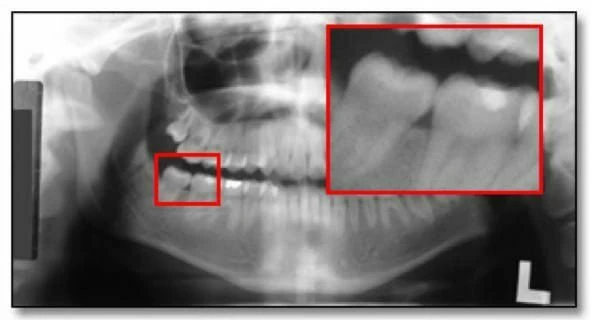

Ví dụ về hình ảnh toàn cảnh thiếu sáng

Hình ảnh với liều tia không đủ có thể dẫn đến không phát hiện được các đặc điểm bệnh lý. Hình 35a là một phiên bản nâng cao kỹ thuật số. Chúng ta có thể dễ dàng thấy chiếc răng hàm thứ ba bên phải bị tác động mà bị mờ đi trên bản gốc. Sự tăng cường này cũng chứng tỏ rõ ràng bệnh nhân có một bệnh lý liên quan đến răng hàm dưới thứ hai bên phải.